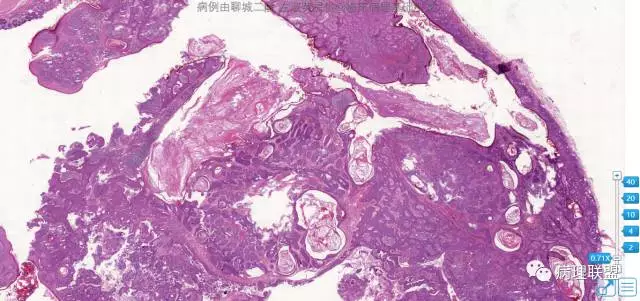

病例1

女,83岁,大腿肿物

图片信息

@左淑英 1毛囊瘤,2毛发上皮瘤。3是钙化上皮瘤。4是外毛根鞘瘤

@左淑英 左老师,您昨晚的第一个病例我弄不清,有大的角化囊,周围有毛发上皮样结构团,请左老师讲解。谢谢左老师!

@刘香丽 五一病例毛囊瘤,并不是一个毛囊,放射不是特别典型,不过还是可以看出来的